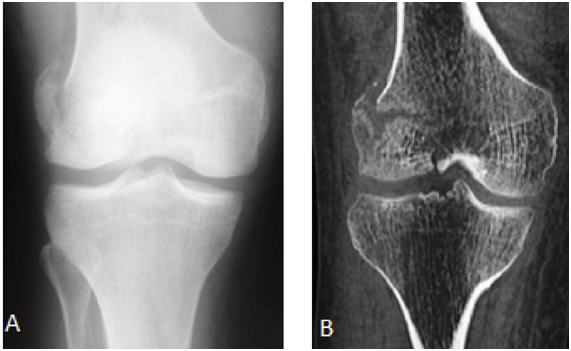

Radiograph of the right knee showed fracture of the posterior aspect of the lateral femoral condyle - Hoffa fracture - type II (Figure 1). CT scan shows fracture of the lateral femoral condyle with a slight misalignment and separation of the fragment, which indicated surgery (Figures 1 & 2). The patient was discharged after surgery, attending since the being accompanied ambulatorially since then (Figure 3).

Figure 2 CT scan in sagital section in A and axial section in shows fracture of the lateral femoral condyle with a slight misalignment and separation of the fragment, which indicated surgery.